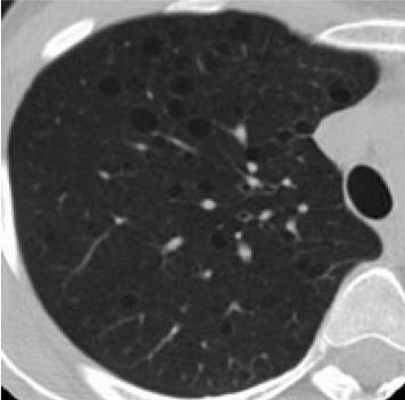

Фрагмент КТ: множественные кистозные изменения - лимфангиомиоматоз легких

• Патология легких:

о Лимфангиолейомиоматоз: редкая диффузная интерстициальная пролиферация гладкомышечных клеток в виде округлых тонкостенных кист

о Множественная мелкоузловая гиперплазия пневмоцитов